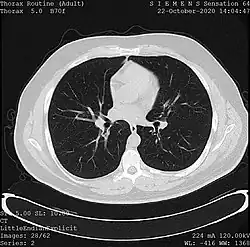

![]() One frame of a CT scan of the chest showing the heart and lungs | |

- X-ray computed tomography (CT), or Computed Axial Tomography (CAT) scan, is a helical tomography technique (latest generation), which traditionally produces a 2D image of the structures in a thin section of the body. In CT, a beam of X-rays spins around an object being examined and is picked up by sensitive radiation detectors after having penetrated the object from multiple angles. A computer then analyses the information received from the scanner's detectors and constructs a detailed image of the object and its contents using the mathematical principles laid out in the Radon transform. It has a greater ionizing radiation dose burden than projection radiography; repeated scans must be limited to avoid health effects. CT is based on the same principles as X-ray projections but in this case, the patient is enclosed in a surrounding ring of detectors assigned with 500–1000 scintillation detectors[13] (fourth-generation X-ray CT scanner geometry). Previously in older generation scanners, the X-ray beam was paired by a translating source and detector. Computed tomography has almost completely replaced focal plane tomography in X-ray tomography imaging.